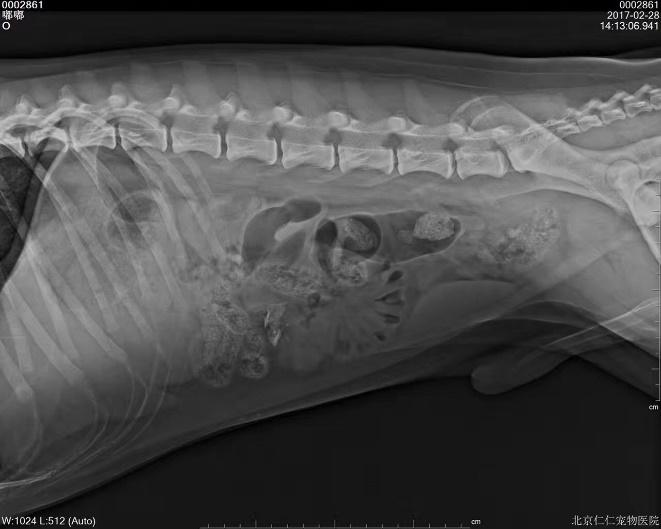

c.X线检查。对于阻线性较强的物质(如金属、骨头)较容易辨别,对于阻线性与组织密度相似的物体较难确定,但是可以通过消化道灌服造影剂判断是否有阻塞或可包裹物体。

机械性肠梗阻的读片要点:1.体积增大;2.形态轮廓变化;3.影像密度变化;4.浆膜细节变化。

金毛 线性异物